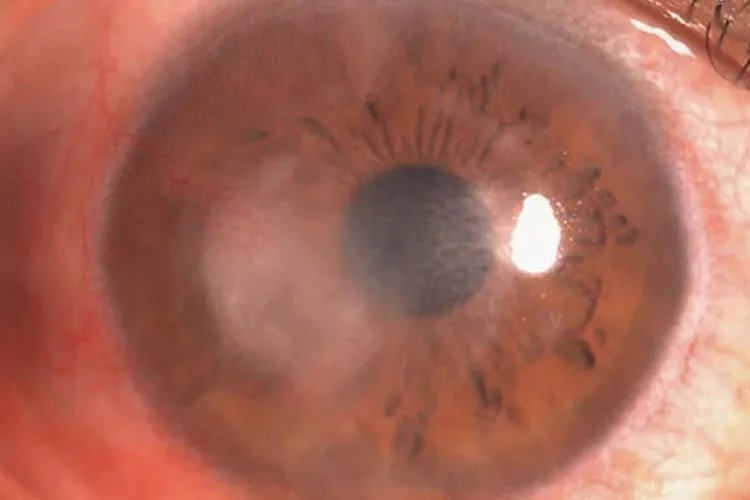

真菌性角膜炎起病缓慢,亚急性经过,临床表现早期症状较轻,发展缓慢,为角膜浅层溃疡。单纯疱疹病毒性角膜炎单纯疱疹病毒性角膜炎中上皮型结膜炎初期病变显著。上皮型角膜炎感染初期角膜上皮层可见灰白色、近乎透明、稍隆起的针尖样水疱,点状或排列成行或聚集成簇,一般仅持续数小时至十余小时,因此常被忽略

非感染性角膜炎角膜基质炎发病初期为单侧,早期可见典型的扇形或弥漫性角膜炎症浸润,可伴有或不伴有角膜后沉着物。

免疫性角膜炎蚕食性角膜炎是最典型、最有代表性的免疫性角膜炎。蚕食性角膜炎病变初期,周边部角膜出现浅基质层浸润,常位于角膜内侧或外侧,随后浸润区出现角膜上皮缺损,继而形成溃疡。